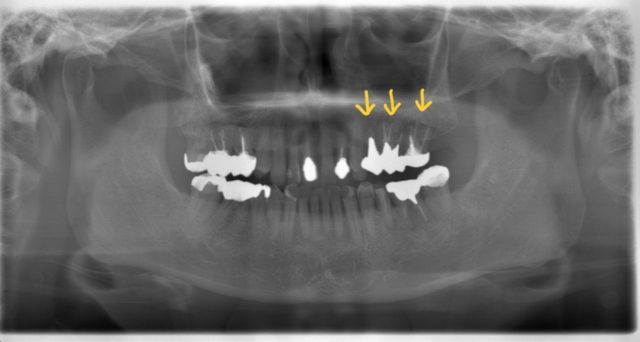

左上臼歯の歯肉が腫れ、他院で抜歯しないといけないと言われた症例です。

左上7番はデンタルX線画像で垂直性の骨吸収が見られる為、歯が破折している場合はインプラントの計画で治療介入をしました。